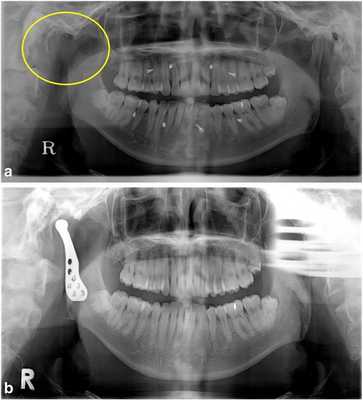

34-летнему мужчине был поставлен диагноз аденоидной кистозной карциномы правого внешнего слухового канала. Ему была проведена операция по удалению карциномы с кондилэктомией правого суставного отростка в отделении отоларингологии (фото 2а). После операции окклюзия стабилизировалась посредством межчелюстных фиксационных винтов и эластичных лент. Ограничений при открытии рта у данного пациента не наблюдалось, однако при открытии рта наблюдалось смещение челюсти в правую сторону. Для поддержки стабильной окклюзии без использования фиксационных межчелюстных винтов через 8 месяцев после первичного вмешательства планировалось провести реконструкцию ВНЧС. После хирургической коррекции сустава межчелюстные винты были удалены, а у пациента было подтверждено стабильное состояние межчелюстного соотношения (фото 2b).

Фото 2.

а) Правый мыщелок был удален (желтый круг) из-за карциномы наружного слухового канала. Для поддержания окклюзии в течение 8 месяцев использовались межчелюстные фиксационные винты и эластичные ленты.

b) Через 1 месяц после реконструкции TMJ фиксационные винты были удалены, а окклюзия оставалась в стабильном состоянии.